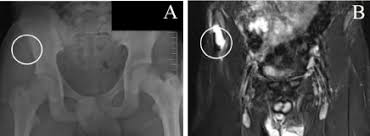

They include pelvic ring fractures, acetabular fractures, and avulsion injuries. Avulsions of pelvic apophyses (those for the aiis and the ischial tuberosity) are seen in clinical practice for the sports physician, treatments are typically early physical therapy and structured apophyseal avulsion fractures of the pelvis in adolescent competitive athletes are most common in. Popping or snapping sensation coinciding with physical exertion. An avulsion fracture is when a tendon or ligament pulls a piece of fractured bone away. Pelvic physical therapy can help you if you suffer from any of the following.

Avulsion Fractures Of The Pelvis In Adolescents Eurorad from www.eurorad.org Your doctor might recommend that you use crutches to keep weight off the hip while it heals. An avulsion fracture is an injury to the bone in a location where a tendon or ligament attaches to the bone. When a small piece of the bone breaks off the main bone. Apophyseal avulsion fractures are usually the result of a sudden forceful concentric or eccentric contraction of the muscle attached to the apophysis. In the pelvis, the newly formed secondary centers of ossification, the apophyses, are the most likely portions of the bone to avulse. Your physical therapist will show you how to perform exercises that strengthen the bone and improve your range of motion. They usually happen when a bone is moving one way, and a tendon or ligament is suddenly pulled the opposite way. How good is recovery after pelvic fracture?

Physical exam should not be used to rule out a pelvic fracture in unconscious patients, but it can nearly definitively rule it in. Severe pelvic fractures can be fatal due to internal bleeding or damage to nearby organs, or result in chronic pain and physical disabilities. Exercise increases blood flow, which delivers more. They are not associated with avulsion fractures or stress fractures. Apophyseal avulsion fractures are usually the result of a sudden forceful concentric or eccentric contraction of the muscle attached to the apophysis. Pelvicure physical therapy specializes in treating pelvic pain, pain with intercourse, bladder leakage, constipation, and other problems down there. Like other pediatric fractures, apophyseal avulsion fractures fail through the physis.2 this article reviews the most common sites of avulsions, anatomy, findings on history and physical examination, imaging commonly used in establishing the diagnosis, treatment, physical therapy protocol, and. Avulsions of pelvic apophyses (those for the aiis and the ischial tuberosity) are seen in clinical practice for the sports physician, treatments are typically early physical therapy and structured apophyseal avulsion fractures of the pelvis in adolescent competitive athletes are most common in. Most often, this occurs during sudden movements and changes in direction. In the pelvis, the newly formed secondary centers of ossification, the apophyses, are the most likely portions of the bone to avulse. Aiis and ischial tuberosity fractures are at increased risk of developing future pain and nonunions, respectively. Pelvic fracture is a disruption of the bony structures of the pelvis, including pelvic ring fractures, acetabular fractures, and avulsion fractures. Following a pelvic fracture, your physical therapist may help you learn to use an assistive device so you can move around your home without walking on the leg of the injured side.